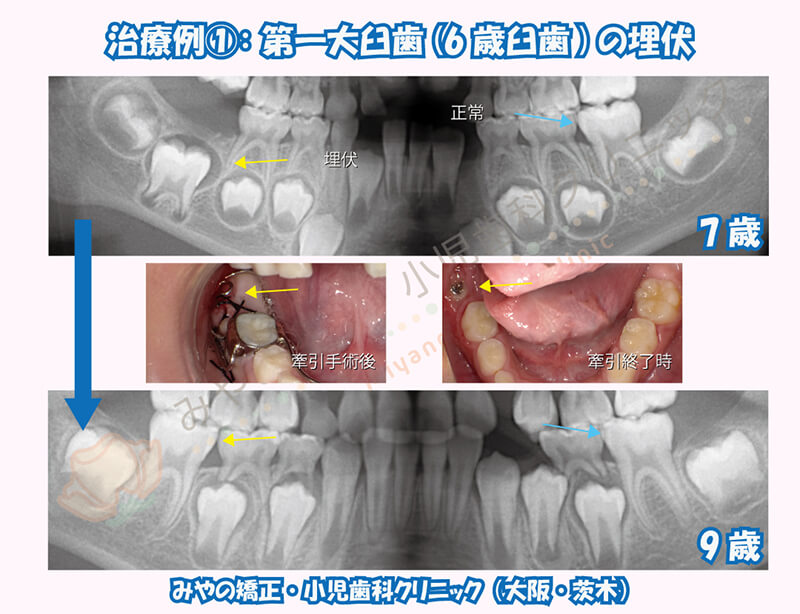

反対側の6歳臼歯はしっかり生えているのに対し、7歳半になっても6歳臼歯が生えてこなかった方です。レントゲン写真にて埋まっている位置がかなり深く、歯の上に歯槽骨もかなり残っている状態でした。

経過観察による自然萌出の可能性と、このまま埋まってしまうリスク、タイミングを逃すと牽引治療が困難になっていくことなど総合的に判断しこの時点で埋伏歯の牽引治療を行うこととしました。牽引は完全に歯が適正な位置に生えるまで行う必要はなく、ある程度出てきた段階で中止し、自然萌出に切り替えましたがきちんと生えてきてくれました。

6歳臼歯が埋伏したままになってしまうと後から生えてくる12歳臼歯が上にかぶさって生えてきたり治療がより複雑化してしまいます。

年齢が高くなってくると牽引治療が困難となるため、埋伏歯の対応は放置もしくは抜歯の2択になってしまうことも多いです。